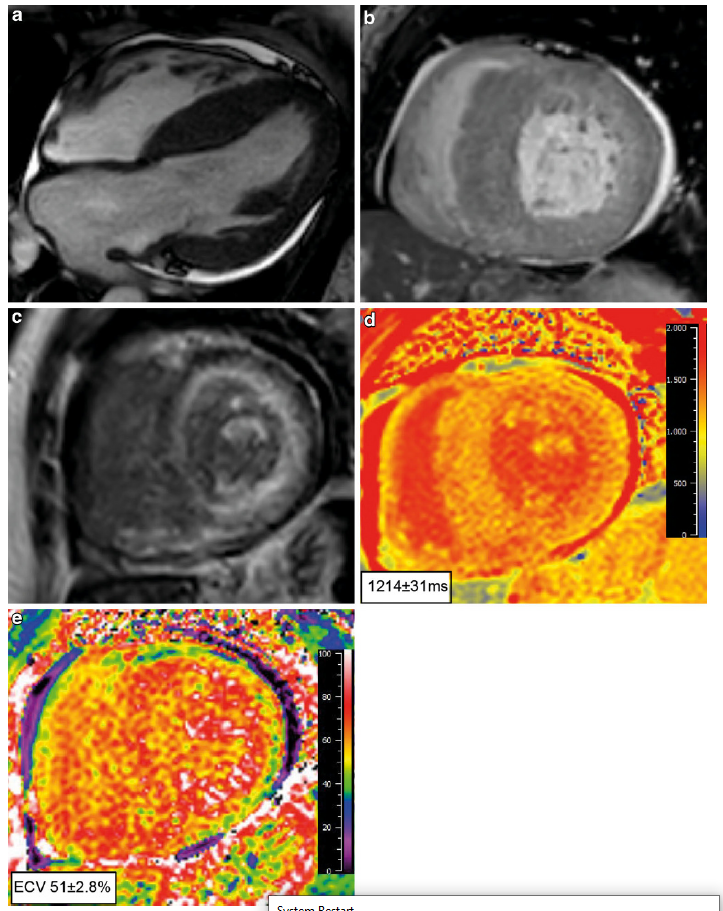

Cardiale magnetische resonantie imaging (MRI)

Ook op de MRI zijn specifieke kenmerken voor ATTRwt zichtbaar. De volgende kenmerken wijzen op ATTRwt:8

- Transmurale of subendocardiale late gadolinium enhancement (LGE), diffuus atriaal LGE, rechter ventrikel LGE en suboptimale nulstelling als gevolg van veranderde gadoliniumkinetiek.

- Verhoogd extracellulair volume (ECV) en verhoogde native T1 waardes.

Figuur 3: cMRI afbeeldingen bij cardiale amyloïdose.

(a,b) een 4-kamer en korte as beeld met linker ventrikel hypertrofie, voornamelijk in de septale regio. (c) Corresponderend korte as beeld dat subendocardiale late gadolinium enhancement laat zien. Let op het verminderde signal van de bloed poel (donker bloed), specifiek voor cardiale amyloïdose (d) Native T1 analyse die een verhoogde T1 weeregeven en (e) verhoogd extracellulair volume. Overgenomen uit Neth Heart J 27, 525 -536 (2019)doi:10.1007/ s12471-019-1299-1 Oerlemans, M.I.F.J., Rutt en, K.H.G., Minnema, M.C. et al. Cardiac amyloidosis: the need for early diagnosis, met toestemming van Bohn Stafl eu van Loghum.